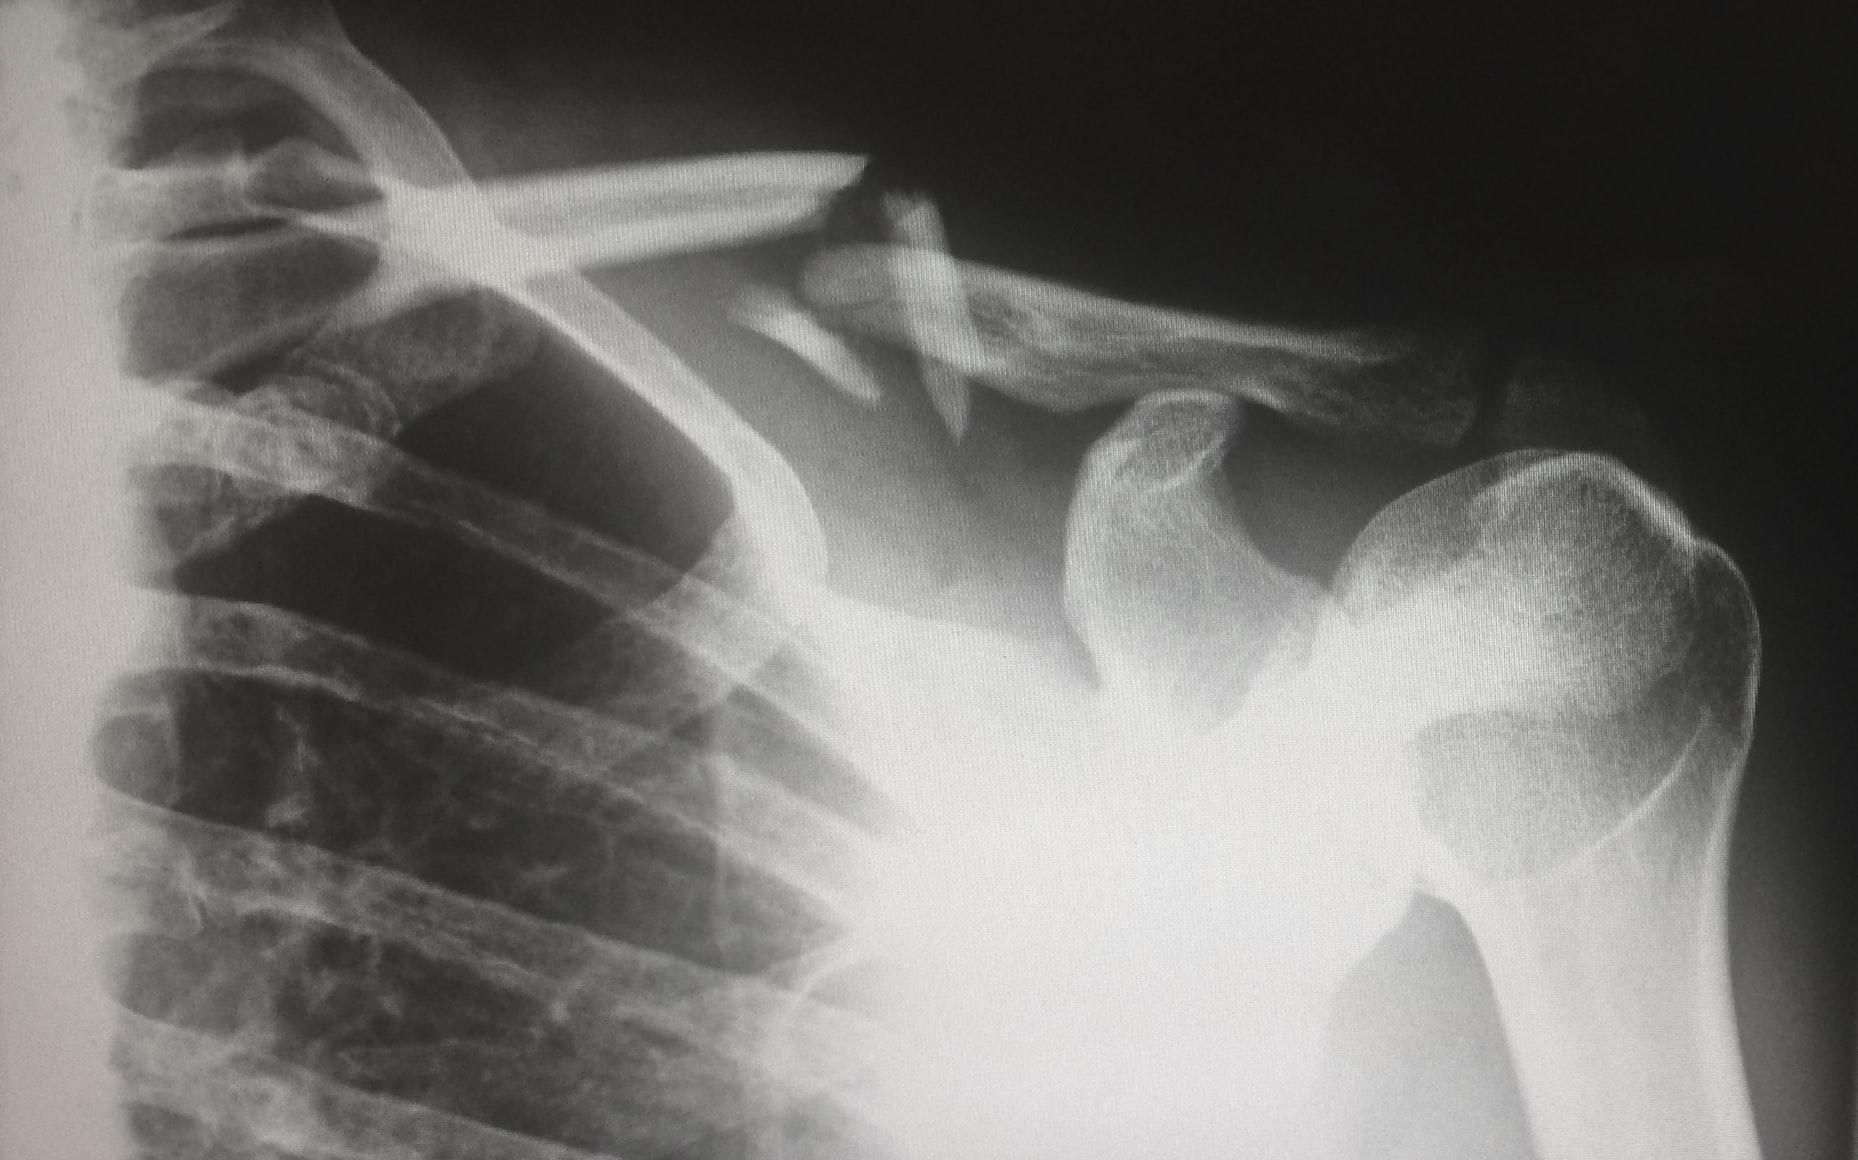

Коротко про регенерацію кісток і чому це складний процес

Людська кістка розвивається одним із двох способів:

- прямим утворенням кісткових клітин із клітин-попередників;

- або шляхом ендохондрального окостеніння – спершу формується хрящ, який потім переходить у кістку.